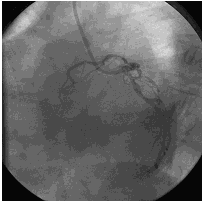

第一次冠脉造影

造影时间:2015年07月17日。

造影结果1:右冠弥漫性病变,近中段90%狭窄。

![]()